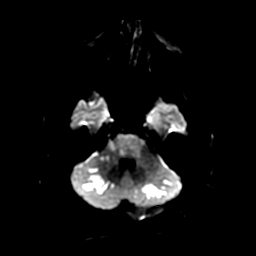

In a procedural suite at UCH, neurosurgeon Joshua Seinfeld, MD, looked at images that showed a complete blockage of Cohen’s left vertebral artery, which supplies blood to the brain stem and left occipital lobe. It had been 14 hours since the clot shut down the artery – a dangerously long period of time. Seinfeld used a stent retriever to pull the blood clot out of the artery, but his work wasn’t finished. The vessel was badly diseased and still couldn’t accommodate much blood flow. Seinfeld performed a balloon angioplasty to widen it.

The stroke damage was extensive, Seinfeld said. Describing Cohen’s case later, he pointed to bright areas on an image of Cohen’s brain – signs of a “completed stroke” that left dead tissue. Had there been more of it, the clot-removal and angioplasty procedures wouldn’t have happened, Seinfeld said.

“Restoring blood flow to dead brain tissue will cause a hemorrhage,” he said. “In [Cohen’s] case, it was risky to remove the clot, and we knew he could do poorly, but if we left it alone, he would die. When there is an occlusion in the areas of the brain where he had his stroke, we tend to consider treatment for a longer period of time than for strokes at the top or the front of the brain because people can have a [much better] response.”

The images of Jim Cohen’s brain showed areas of distinct light and dark – the clearly defined lines of tissue life and death. But there were also shades of gray, areas where the two intersected. Those patches defined the uncertainty that awaited Cohen after Seinfeld finished the procedure.